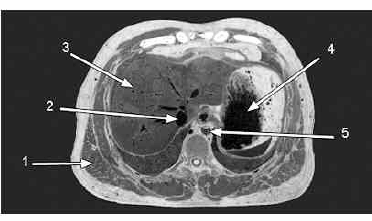

A figura acima mostra a fotografia de um corte anatômico realizado em cadáver. Considerando os dados mostrados na figura, julgue os itens a seguir.

A área mais clara que circunda todas as estruturas indicadas por setas é composta por tecido ósseo.

A seta 5 indica a aorta descendente.

A seta 4 indica a cavidade interna de um órgão.

A seta 3 indica um órgão capaz de realizar trocas gasosas.

A seta 2 indica a traquéia.

A seta 1 indica o músculo grande dorsal.

A figura mostra um corte transversal, aproximadamente no nível da 11.ª vértebra torácica.